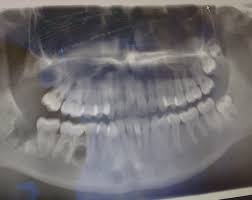

Der Arzt hat das unterste Stück der Wurzel stehen gelassen da es etwas verwachsen sei und zu nah am Nerv. Mir wurde am Mittwoch 214. Dieser entscheidet ob eine operative Entfernung des Zahnes notwendig ist.

Häufig verläuft ein Nerv entweder durch die Wurzeln oder am Zahn entlang. Und bei nicht wenigen war es der fall dass der eingriff nah am nerv vorgenommen wurde das risiko also da war. Bevor ich meinen körper über jahre mit schmerzmitteln schädige und schmerzen leide würde ich mich diesem eingriff unterziehen.

Sie liegen sehr nah am Nerv weshalb der Arzt nur zwei auf Einmal zieht. Bei der lokalen Narkose besteht das Risiko vor allem dadurch dass durch die Nadel ein Nerv beschädigt wird.